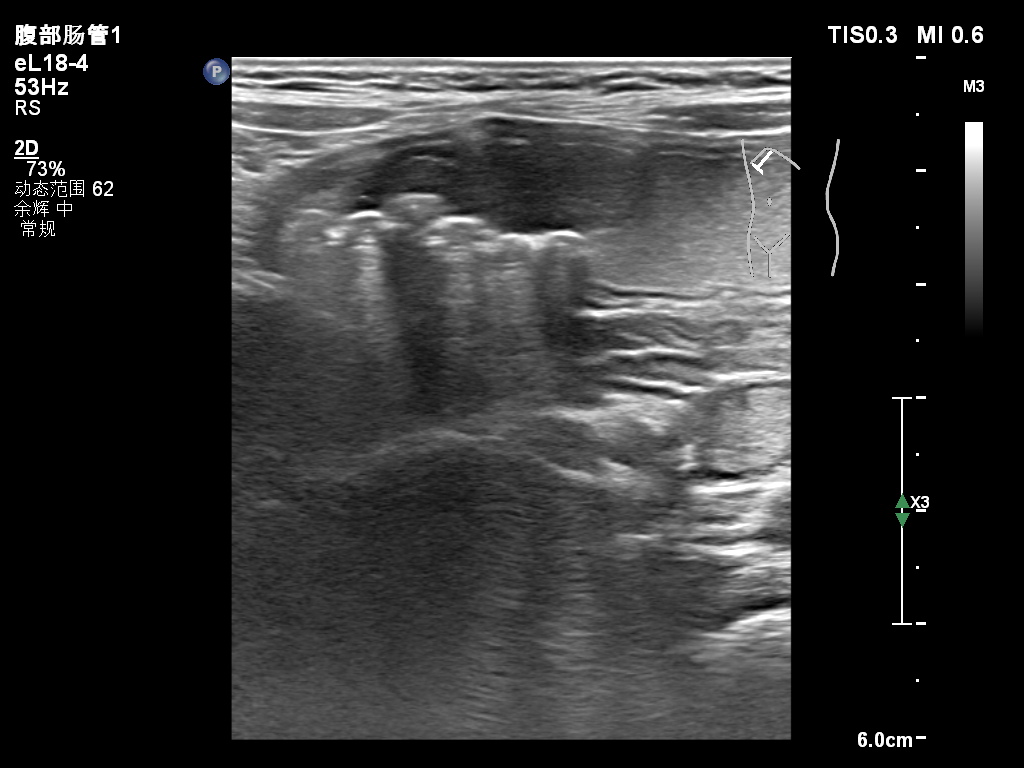

胃內異物—磁力珠